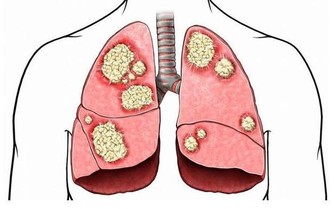

還需注意,2型糖友有可能出現夜間血糖過高,原因是使用降糖藥物劑量不足、晚餐吃得過多、餐後運動量過少等,長此以往將出現糖尿病相關的慢性並發症如糖尿病腎病等。

如果血糖驟然升高還可能會出現急性並發症如糖尿病酮症酸中毒,影響患者的生活質量和預期壽命。夜間高血糖易出現多尿、口渴,導致糖友如廁和飲水增加,影響睡眠。糖友可遵醫囑改進生活方式、調整治療方案,從而控制血糖以利安眠。